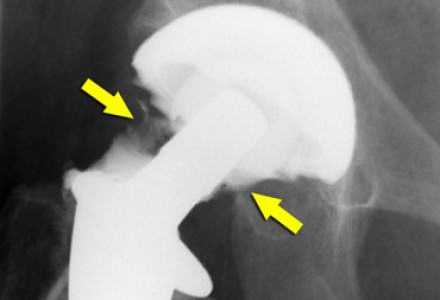

(Слева) МР-артрография в режиме Т1ВИ FS, коронарный срез: визуализируется неоднородное скопление контрастного препарата, распространяющееся через разорванную подвздошно-бедренную связку за пределы суставной капсулы.

(Справа) Артрография, передне-задняя проекция: определяется небольшой затек контрастного препарата через подвздошно-бедренную связку, обусловленный тем, что после артроскопической операции дефект суставной капсулы не был закрыт. Пациент ощущал нестабильность сустава.

(Слева) МР-артрография в режиме Т1ВИ FS, аксиальный срез: визуализируется отграниченное скопление контрастного препарата Si за пределами заднего отдела суставной капсулы, обусловленное разрывом седалищно-бедренной связки вследствие травматическою заднего вывиха бедра. Видны разорванные волокна седалищно-бедренной связки. В вертлужной ямке выявляются свободные хрящевые тела.

(Справа) МР-артрография в режиме PD FS, сагиттальный срез, этот же пациент: отмечаются нарушение целостности седалищно-бедренной связки и распространение контрастного препарата кзади.